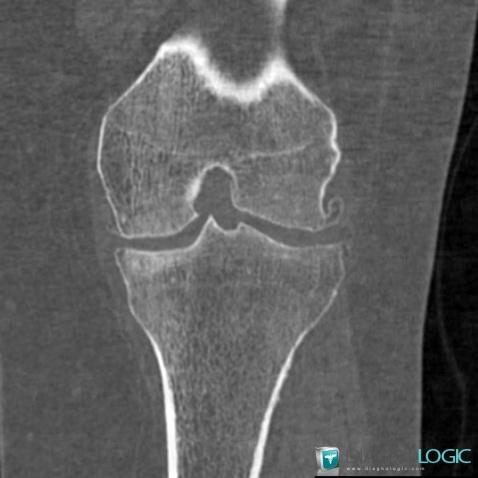

Arthrose, Articulations fémoro tibiales / Echancrure, Scanner

Voici les informations spécifiques à l'image clé ci dessus:

- Diagnostic Arthrose, Localisation(s) Articulations fémoro tibiales / Echancrure, comportant les gammes